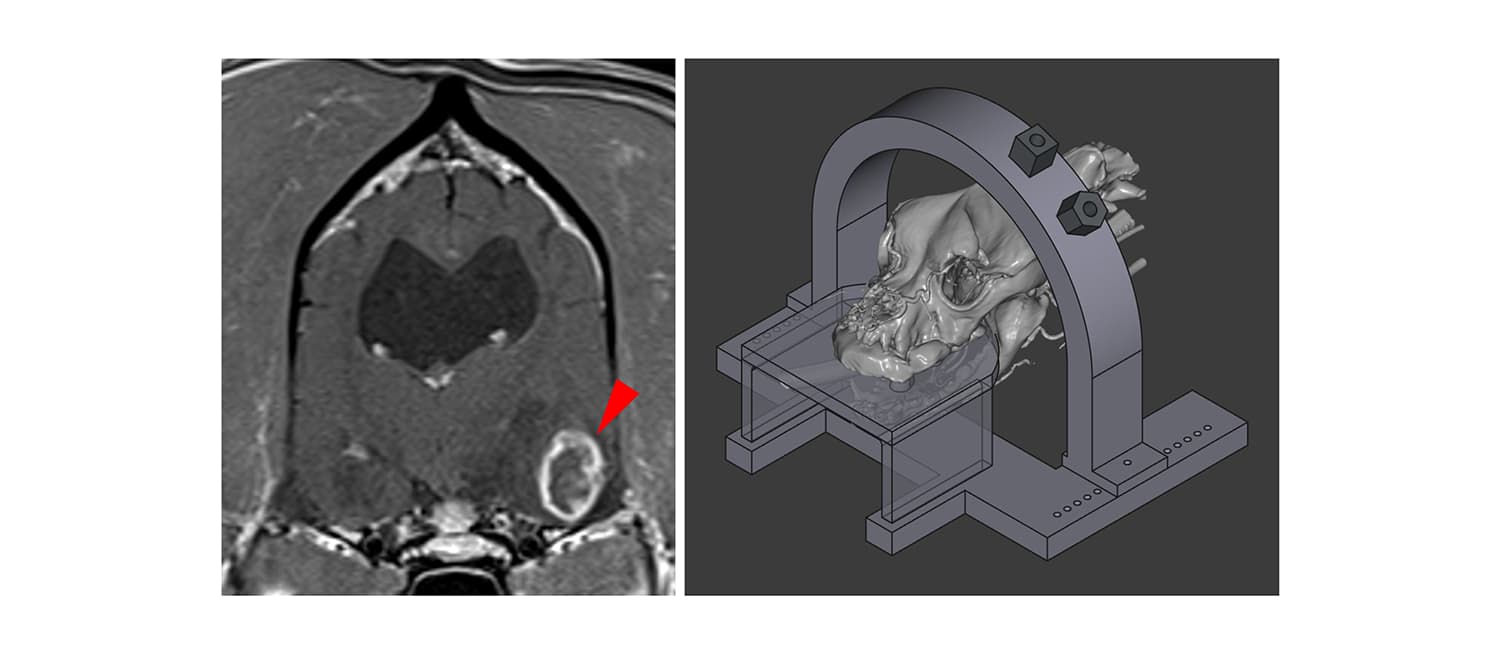

Brain Tumor Biopsy Approach Posted on May 13, 2025May 14, 2025 by noliver Developing personalized 3D printed devices that will permit minimally invasive brain biopsies Return to Research